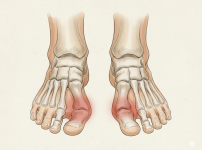

리스프랑 인대 파열 및 발등뼈 골절(Lisfranc joint injury) | 서울건우 | 의학정보

정의발등은 무수히 많은 뼈와 인대가 복합적으로 얽혀 아치를 유지하고 체중을 지탱하는 핵심 부위입니다. 리스프랑(Lisfranc) 관절은 발등 중간에서 발가락 뼈(중족골)…